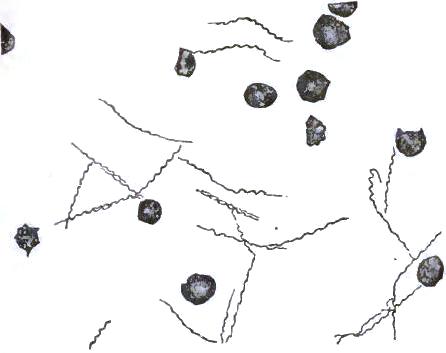

| FIGURE | |

| 1. | MICROCOCCI |

| 2. | BACTERIA |

| 3. | BACILLUS MALARIÆ |

| 4. | BACTERIA FROM GELATIN SOLUTION |

| 5. | VIBRIOS IN GELATIN CULTURE-FLUID |

| 6. | PROTOCOCCUS FROM SLIDES EXPOSED OVER SWAMP-MUD |

| 7. | BACILLI FROM SWAMP-MUD |

| 8. | BACILLI FROM SEPTICÆMIC RABBIT |

| 9. | BACILLI FROM HUMAN SALIVA |

| 10. | BACILLUS ANTHRACIS |

| 11. | BACILLUS TUBERCULOSIS |